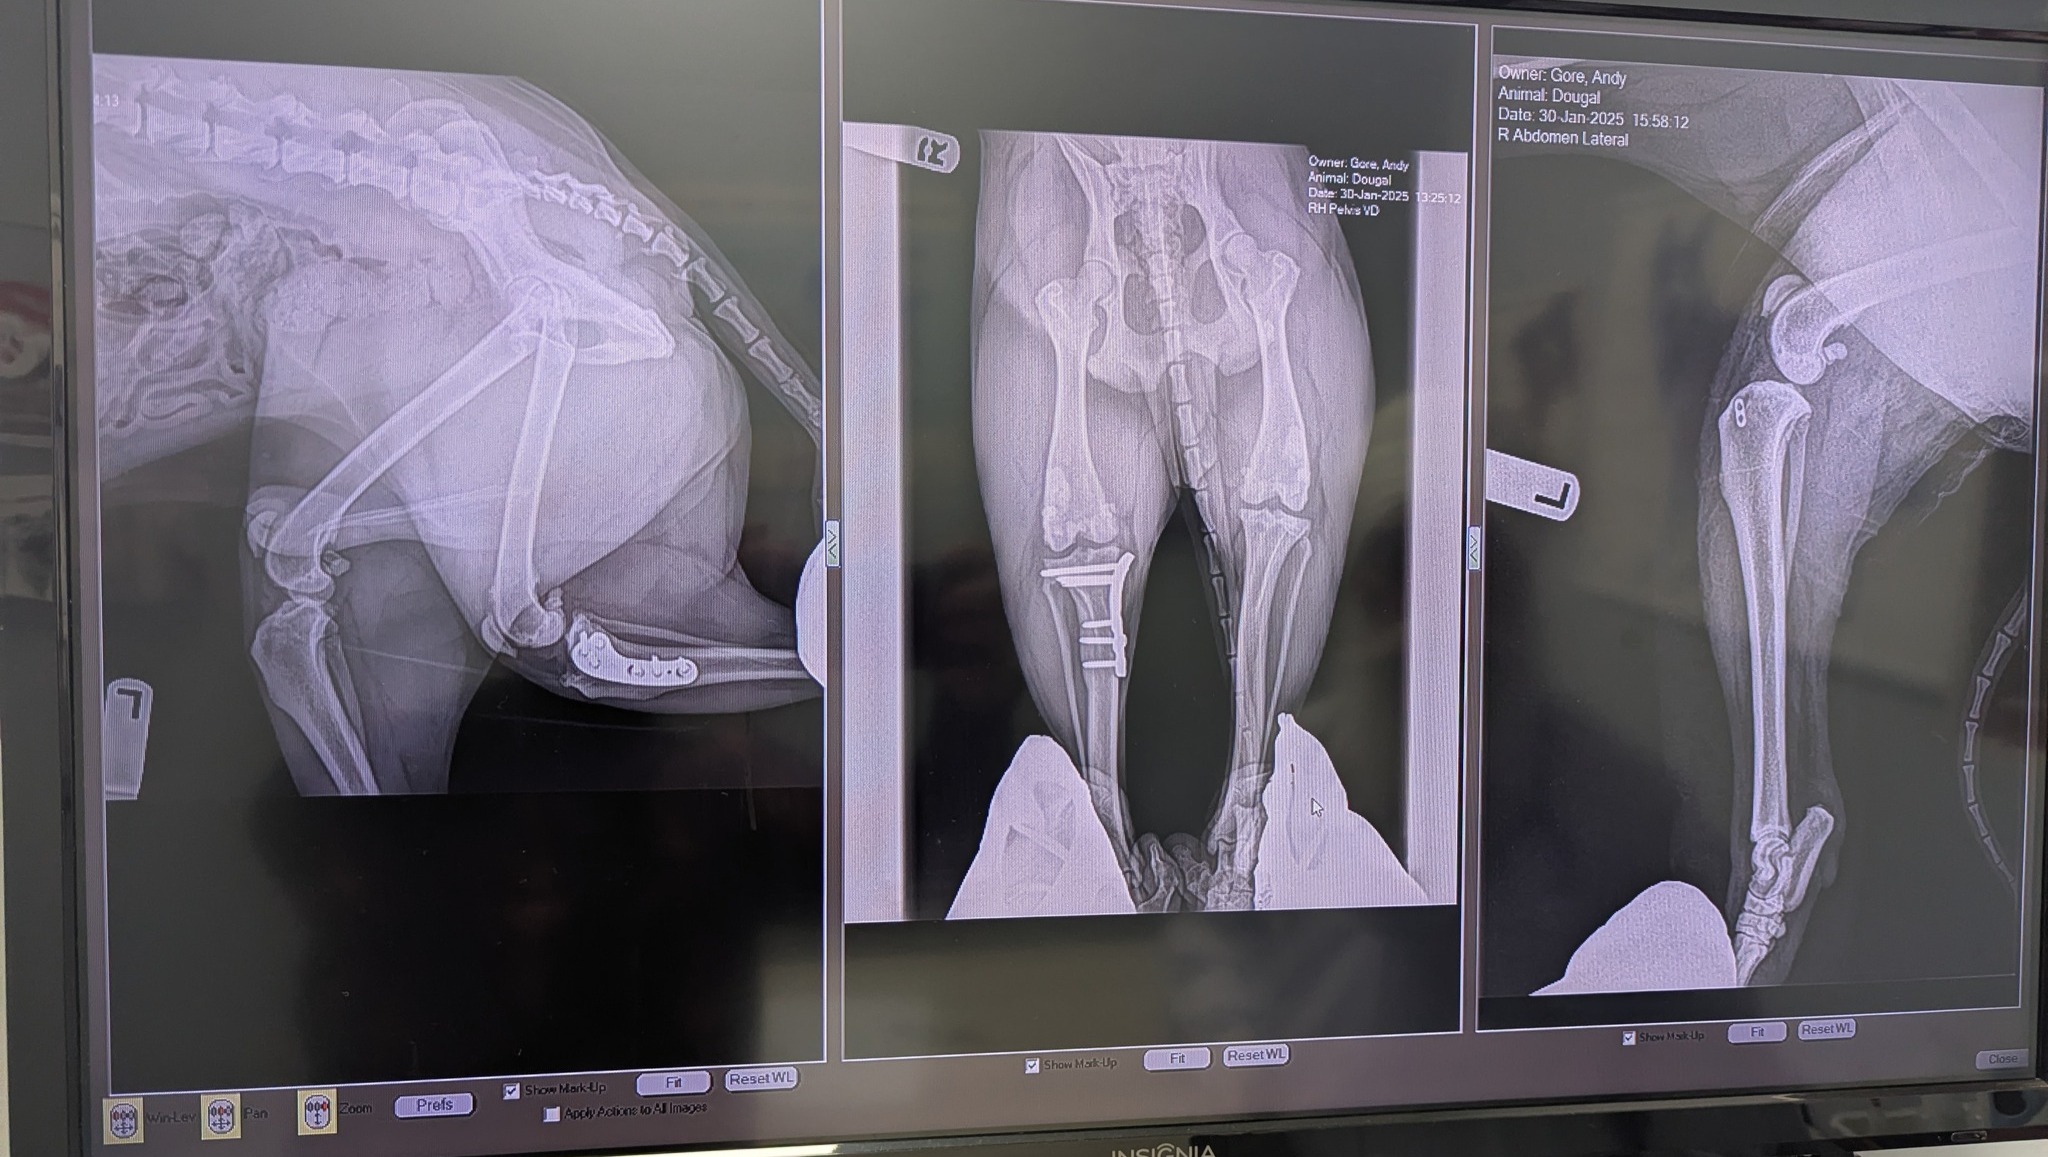

As Dougal aged, his 2023 right knee TPLO surgery and 2025 ECR left knee repair along with 6 medications that manage his osteoarthritis pain have depleted the medial funds Dana & I set aside for him substantially.

He wasn't about to walk. At all. He fully snapped the ligament that holds his left knee joint together (CCL, or canine version of an ACL), and was unable to put any weight into that leg.

Dougal's Right knee was fully rebuilt 2 years ago. Now that he is 9.5 yrs old with arthritis in all other legs & his spine, lumbosacral disease, and chronic tendonitis in both front legs, amputation wasn't an option.

Dr John Brajkevic at Caledon Mountain Animal Hospital completes Dougal's right knee surgery. Due to the knee "hanging on by a thread" Doougal undergoes extremely invasive & intense TPLO for a 85%+ CCL tear).